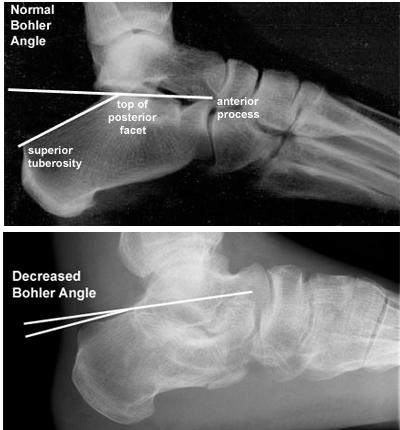

当跌倒后出现足后跟剧烈疼痛,局部肿胀及瘀斑明显,跟骨压痛,无法下地行走,应高度怀疑跟骨骨折,要马上到医院确诊(拍X光片,跟骨正侧位+轴位片)。对于严重的粉碎性或者波及关节面的骨折,最好还要做个CT,指导具体手术方案。

跟骨骨折需要恢复的角度